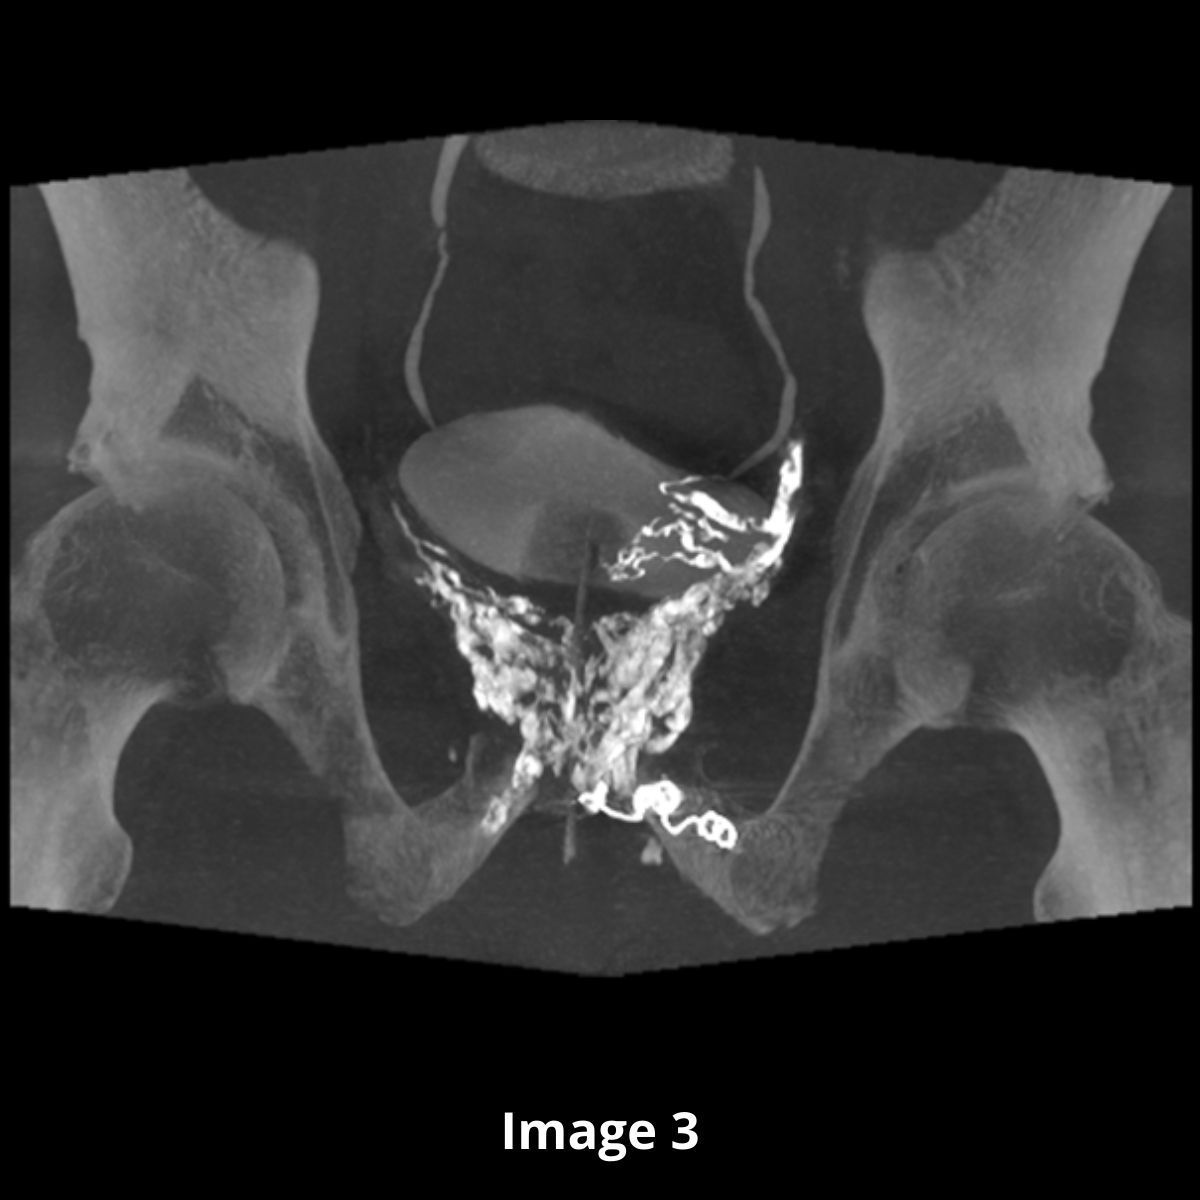

Nous procédons donc à une embolisation par agent liquide (lave) avec un résultat optimal (image 2 en graphie et image 3 en CBCT reconstruction coronale).